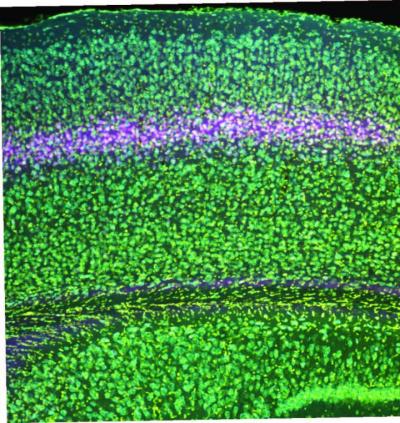

Researchers used a genetic technique to knock out NMDA receptors in layer 4 of the visual cortex of mice. Credit: Bear Lab/ Picower Institute for Learning and Memory.

MIT Professor Mark Bear’s lab has discovered new cellular mechanisms serving visual recognition memory, in which the brain learns what sights are familiar so it can focus on what’s new, and of a potential therapy for amblyopia, a disorder where children born with disrupted vision in one eye can lose visual acuity there permanently without intervention. Both of these depend on the presence of NMDA receptors in the neurons in layer 4 of the cerebral cortex, an area that is thought to directly receive visual information.